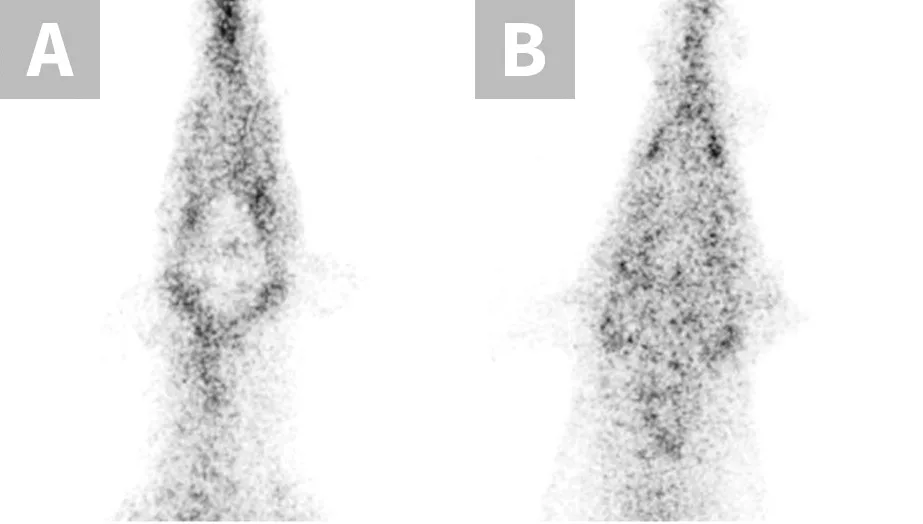

P-glycoprotein, encoded by the multidrug sensitivity gene (MDR1 gene, also known as ABCB1 gene), functions as a drug transport pump at the blood-brain barrier, preventing potentially toxic compounds from gaining access to the brain.1 The MDR1 gene mutation (ABCB1-∆) results in production of dysfunctional P-glycoprotein and affects many herding breed dogs (Table 1) and some nonherding breeds.2 Drugs that are P-glycoprotein substrates achieve higher brain concentrations in dogs with the MDR1 mutation (heterozygous or homozygous) than in dogs without the mutation.1 When P-glycoprotein substrate drugs exert CNS effects, those effects are more pronounced in dogs with the MDR1 mutation unless the dosage is decreased appropriately.1,3 Thus, dose reductions should be made when possible or an alternative drug should be selected. A nuclear scintigraphy study demonstrated that wild-type MDR1 homozygotes (MDR1 normal/normal) have a fully functional blood-brain barrier with essentially no radioactivity in the brain, whereas MDR1 mutant homozygotes (MDR1 mutant/mutant) have brain radioactivity levels comparable with surrounding tissue, demonstrating a dysfunctional blood-brain barrier with respect to P-glycoprotein substrates (Figure 1).1 Although many P-glycoprotein substrate drugs (Table 2) exert CNS effects and cause neurologic toxicity in dogs with the MDR1 mutation, some do not and can therefore be administered at usual dosages. MDR1 genotyping should be performed to identify at-risk dogs prior to treatment with P-glycoprotein substrate drugs.4

FIGURE 1

Nuclear scintigraphic images of the brain and surrounding tissue in collies after IV injection of the radiolabeled P-glycoprotein substrate sestamibi (99mTc-sestamibi). P-glycoprotein restricts 99mTc-sestamibi entry into brain tissue of the MDR1 wild-type dog (A), whereas lack of P-glycoprotein allows 99mTc-sestamibi to enter brain tissue of the MDR1 mutant/mutant dog (B).